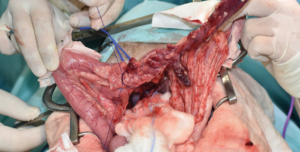

La tomografía computarizada (TC) puede ser particularmente útil en la investigación de insulinomas, puesto que el gas en el tracto gastrointestinal no supone una limitación y es una prueba más sensible en la identificación de pequeñas lesiones, aunque para ello se suele necesitar la TC de fase dual. El insulinoma se caracteriza por presentar una imagen de nódulo hipoatenuante con un gran refuerzo, únicamente en la fase arterial del estudio (halo de contraste alrededor del nódulo) y no en otras fases (imagen 1).